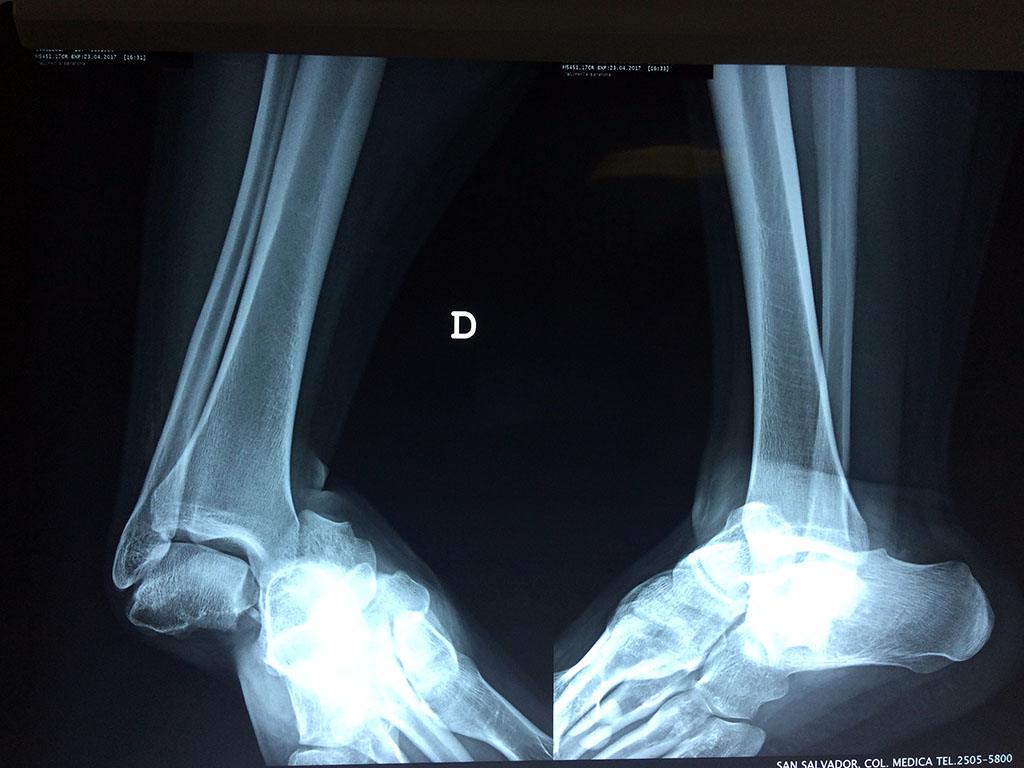

Una fractura de tobillo es la rotura de uno o más de los huesos del tobillo. Estas fracturas pueden ser:

- Parciales (el hueso está sólo parcialmente fisurado, no del todo).

- Completas (el hueso está perforado y está en 2 partes).

- Producirse en uno o ambos lados del tobillo.

Algunas fracturas de tobillo pueden requerir cirugía si:

- Los extremos de los huesos están desalineados entre sí (desplazados).

- La fractura se extiende hasta la articulación del tobillo (fractura intra-articular).

- Los tendones o ligamentos (tejidos que sujetan los músculos y los huesos entre sí) están rotos.

Cuando se necesita cirugía, es probable que esta implique el uso de clavijas de metal, tornillos o placas para sostener los huesos en su lugar mientras la fractura se consolida. Los elementos de soporte pueden ser temporales o permanentes.